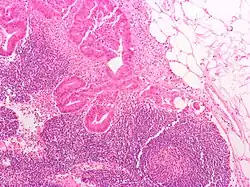

O tipo do tumor é geralmente diagnosticado através da análise de tecido removido através de uma biópsia ou cirurgia. O diagnóstico patológico geralmente contém a descrição histológica do cancro, e o grau. O tipo mais comum de cancro colorretal é adenocarcinoma, que compõe 95% dos casos - acredita-se que a maioria dos casos de cancro colorretal envolvam tumores originários de pólipos adematosos. Outros tipos, mais raros, de cancro colorretal, incluem linfoma e carcinoma espinocelular. As causas do cancro colorretal não são conhecidas com exatidão no presente.

Adenocarcinoma é um tipo de tumor maligno epitelial, que se origina do epitélio glandular da mucosa colorretal. Tal tumor invade a parede, infiltrando a mucosa muscular, a submucosa, e daí, a muscularis propria. As células do tumor abrigam estruturas tubulares irregulares, de estrutura pluristratificada, lúmens múltiplos, e estromas reduzidos. Por vezes, as células do tumor secretam muco, que invade o fluido intersticial, produzindo grandes agrupamentos de muco e colóide (que, visualmente, aparecem como "espaços vazios") - é o chamado adenocarcinoma colóide, pouco diferenciado. Se o muco permanece dentro da célula do tumor, o muco empurra o núcleo celular para a periferia da célula - célula do tipo signet-ring. Dependendo da arquitetura glaudular, pleomorfismo celular, e padrão da secreção de muco, o adenocarcinoma pode ser categorizado em três graus de diferenciação: bem diferenciado, moderadamente diferenciado, e mal diferenciado.[48]